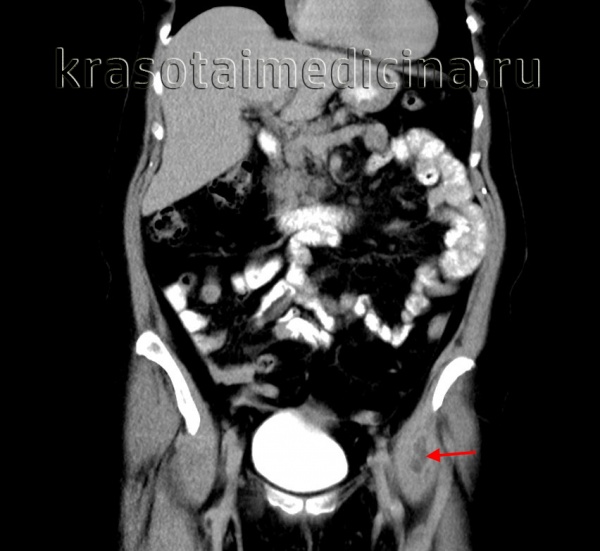

КТ живота и таза. Ограниченное гиподенсное скопление жидкости в толще левой подвздошно-поясничной мышцы (псоас-абсцесс).